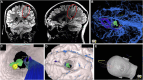

Objective: To describe a case series showing the application of immersive VR involving both "top-down" from skull to lesion and "bottom-up" from lesion to skull approaches for trajectory planning in pediatric neurosurgical patients.

Methods: We detail the preoperative and intraoperative application of VR and clinical courses of 5 children (aged 7-14 years) with anatomically challenging intraparenchymal lesions that posed operative risks to nearby vascular anatomy and fiber tracts. Preoperative planning consisted of standard presurgical evaluation with computed tomography and magnetic resonance imaging used to render 3-dimensional models that could be viewed and manipulated using desktop software and immersive VR headsets and hand controllers by the surgeon and family. Patient satisfaction was evaluated by survey. Surgical outcomes were degree of seizure control or extent of resection.

Results: Three patients underwent lesion resection and 2 laser ablation. Modifications to 2-dimensional and "top-down" VR trajectory plans were made after "bottom-up" navigation in all cases. All families reported that the VR enhanced their understanding of the procedure. There were no complications, and no patients suffered permanent neurological deficits postoperatively. Gross total resection was achieved in all lesional cases, and patients with epilepsy achieved seizure freedom at 2 years postoperatively.

Conclusion: Immersive VR allows operative corridors to be virtually traveled and viewed from a "top-down" and "bottom-up" perspective, as if looking up from under a forest canopy of overlying anatomy, for optimal trajectory planning and improvement of family understanding in pediatric neurosurgery.